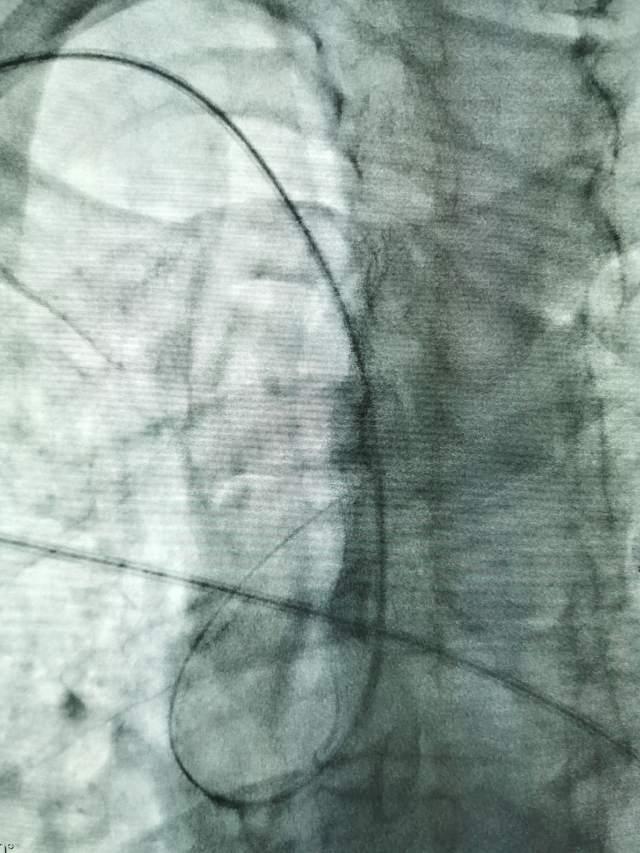

鉴于老人家体质虚弱,走路不方便,疫情期间,家人又不方便陪同,我们采用最微创的远侧桡动脉入路为老人家做了进一步检查,血管真的很扭哈,老人家也听不清楚,检查期间动来动去的,结果发现:下水道(深浅静脉系统有血栓堵塞)不通畅哦,次日给予了药物调整。治疗3天后,老人家听力明显改善,可以和医生自由交流,下床走路也如履平地,完全换了一个人哈~~~